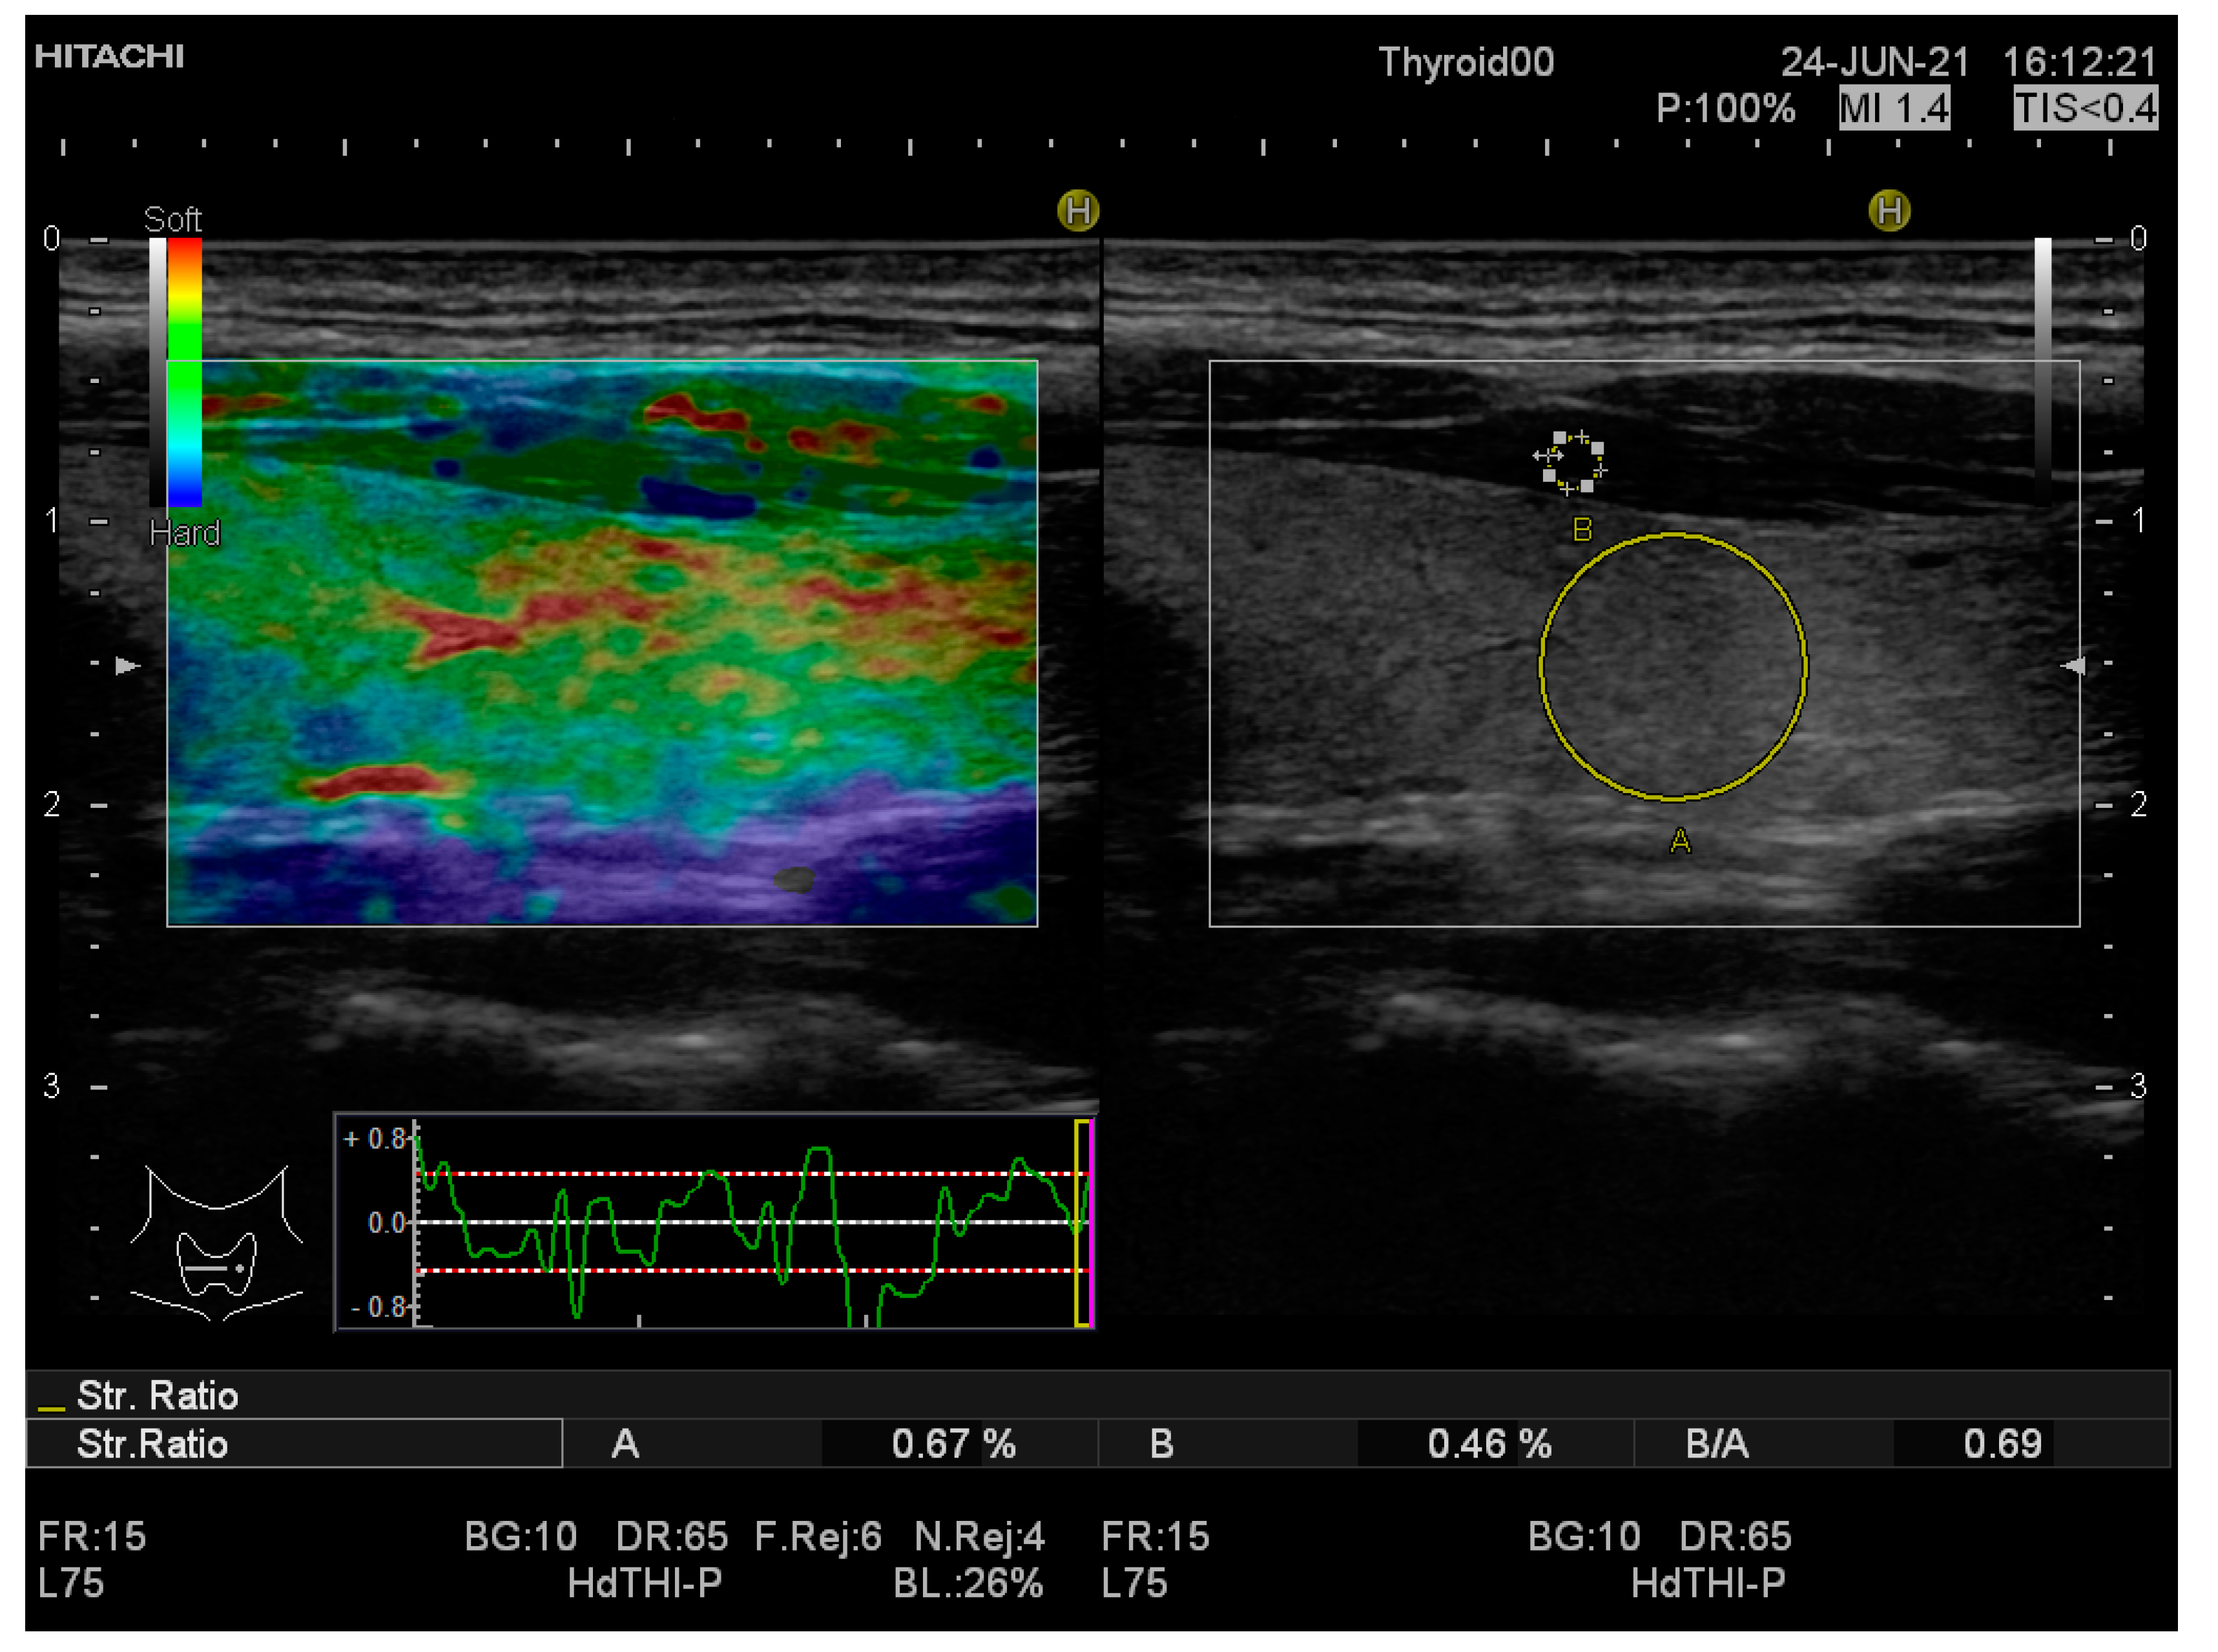

| SR mean value | 1.19 ± 0.25 | 0.68 ± 0.2 | <0.0001 |

| SR-LTL | 1.20 ± 0.31 | 0.66 ± 0.19 | <0.0001 |

| SR-RTL | 1.18 ± 0.27 | 0.70 ± 0.24 | <0.0001 |